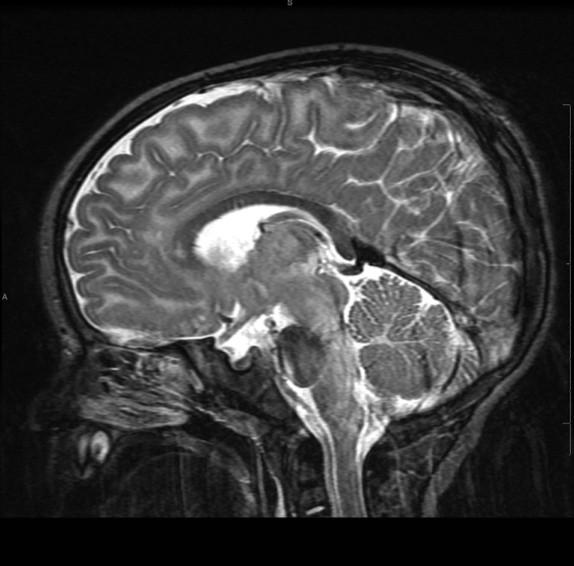

“White Brain”

ROI #1: Basal Ganglia

Single Voxel MRS Spectrum automatically generated, saved to PACS.

MRS ROI #2: Watershed White Matter

Multivoxel : Remember to manually screen save your ROI image.